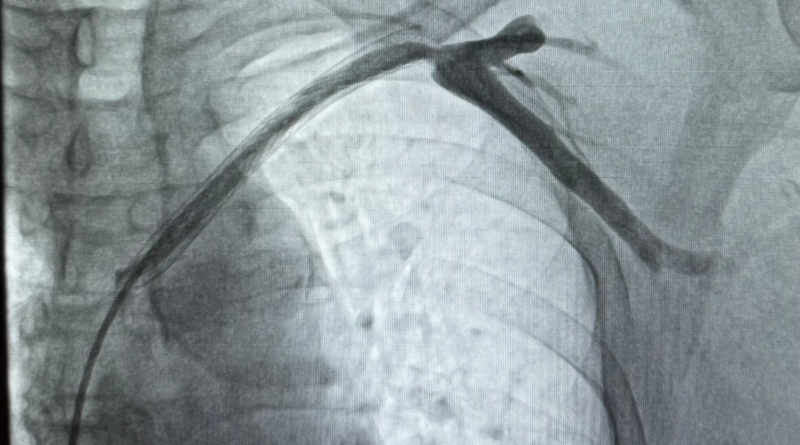

BỆNH VIỆN C ĐÀ NẴNG: CAN THIỆP THÀNH CÔNG CA THUYÊN TẮC TĨNH MẠCH CHI TRÊN ĐẦU TIÊN TẠI MIỀN TRUNG

Lần đầu tiên tại Đà Nẵng, các bác sĩ Bệnh viện C đã can thiệp tái tạo thành công dòng chảy tĩnh mạch cho bệnh nhân suy thận mạn bị tắc nghẽn stent hoàn toàn. Thành công này mở ra cơ hội điều trị tại chỗ với chi phí thấp cho người bệnh khu vực miền Trung – Tây Nguyên.